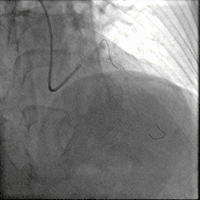

于前降支中段近段口串联2.5mm×18mm、3.0mm×18mm DES。

前降支开口精确定位植入3.5mm×18mm DES。

2.5mm-3.5mm后扩球囊后扩张。

最终结果满意,复查IVUS支架膨胀、贴壁良好!